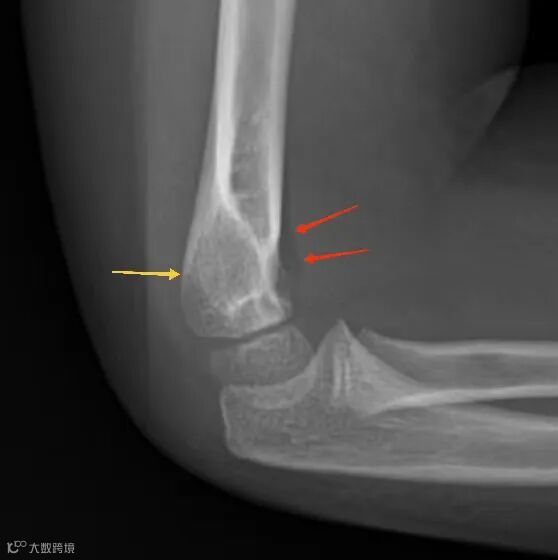

正常肘关节X线侧位,前脂肪垫(红色箭头)为紧贴肱骨的一条细线状或窄三角形低密度影,后脂肪垫(黄色箭头)看不见。

当前脂肪垫变得突出、抬高,像一个扬起的船帆时,即为阳性。这被称为帆征或三角帆征。

前脂肪垫征阳性提示关节腔内压力增高,通常是由于积液(血液或关节液)将脂肪垫从冠突窝里推了出来。

在成人中,提示桡骨头骨折;而在儿童中,最常见的原因是肱骨髁上骨折。

敏感性强,但特异性稍差。只要关节内有较多积液,它就可能出现。